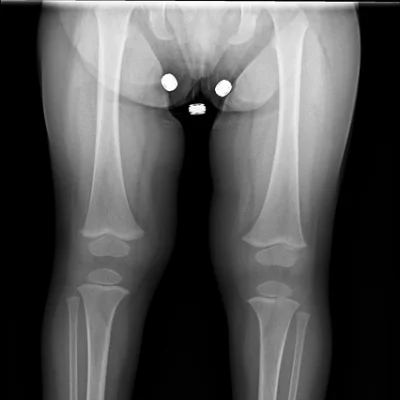

Limb X-Ray

Evaluation of bones and joints in arms and legs for fractures, arthritis, or deformities.